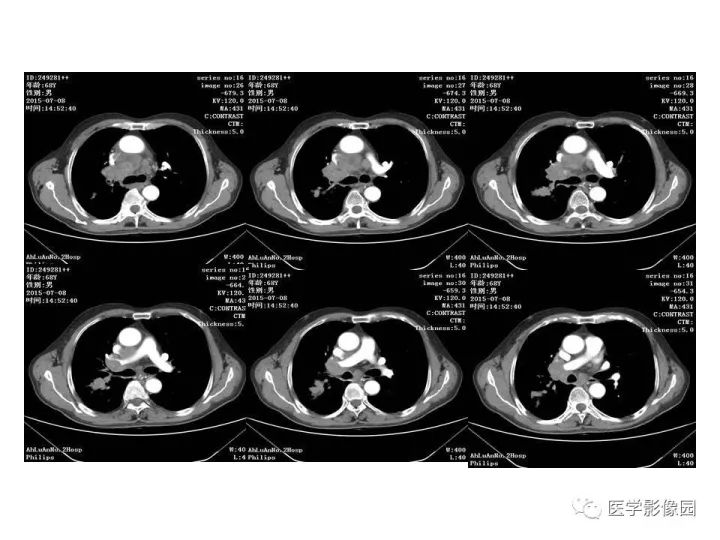

【病例】右肺上叶小细胞癌1例CT影像表现

【病例】右肺上叶小细胞性肺癌1例CT影像表现